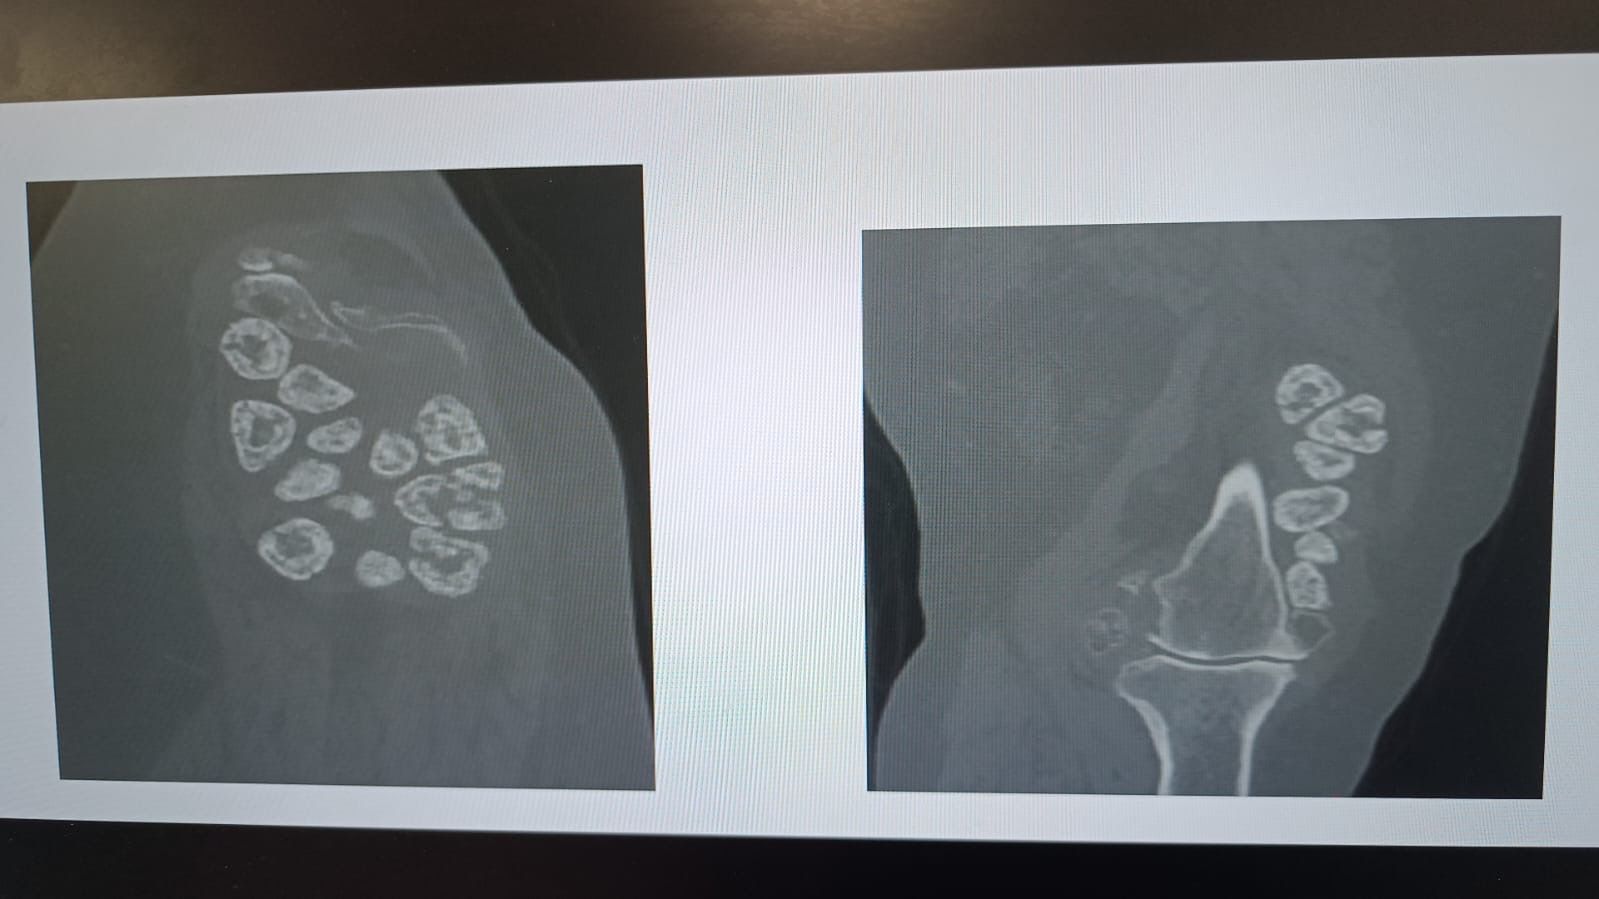

Moderator.az xəbər verir ki, İnönü Universiteti Turgut Özal Tibb Mərkəzində həyata keçirilən uğurlu əməliyyat zamanı Büyükbirerin dizindən 24 ədəd daşlaşmış şiş çıxarılıb. Uzun illər ağrıdan əziyyət çəkən və gəzə bilməyən Elif Büyükbirer çarəni Turgut Özal TibbMərkəzində tapıb. Aparılan ətraflı müayinələrdə xəstənin diz oynağında xəmirləşmiş dərəcədə kalsifikasiya, həm də nadir rast gəlinən “sinovialkondromatoz” adlı xəstəlikdən yaranmış çox sayda daşlaşmış şiş aşkarlanıb. Ortopediya və travmatologiya üzrə mütəxəssis prof. Dr. Reşit Sevimli tərəfindən həyata keçirilən əməliyyatda xəstənin dizindən 24 ədəd daşlaşmış şiş təmizlənib. Həmçinin eyni vaxtda total diz protezi də tətbiq edilib.

Prof. Dr.Sevimli əməliyyatın çox nadir bir hadisə olduğunu qeyd edib: “Elif xanımın dizində həm şiş, həm də kalsifikasiya mövcud idi. Bu iki halın eyni anda baş verməsinə çox nadır hallarda rast gəlinir. Diz oynağından "oynaq daşları"’ adlandırdığımız 24 ədəd kütlə çıxardıq. Daha sonra total diz protezi əməliyyatını da həyata keçirdik. Hazırda xəstəmiz rahat şəkildə gəzə bilir.”

Professor əməliyyatdan sonra xəstənin vəziyyətinin yaxşı olduğunu bildirib: “Adətən bu tip hallarda bir və ya iki şiş olur, lakin bu xəstəmizdə tam 24 daşlaşmış kütlə aşkarladıq. Xəstə indi dizini rahat hərəkət etdirə bilir və qısa müddətdə xəstəxanadan çıxarılacaq. Bu tip xoşxassəli şişlərdə belə erkən diaqnoz çox önəmlidir. Elif xanıma diaqnoz bir qədər gec qoyulmuşdu, amma sürətli müdaxilə ilə uğurlu nəticə əldə etdik.”